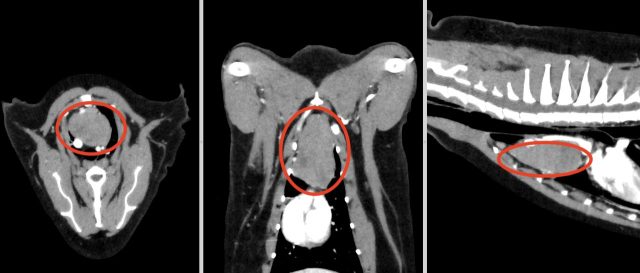

・CT検査:大きさや広がり、リンパ節転移、遠隔転移の評価

※CT検査はより綿密な治療方針を決定するうえで推奨される検査です

胸腺腫のCT画像(赤丸)